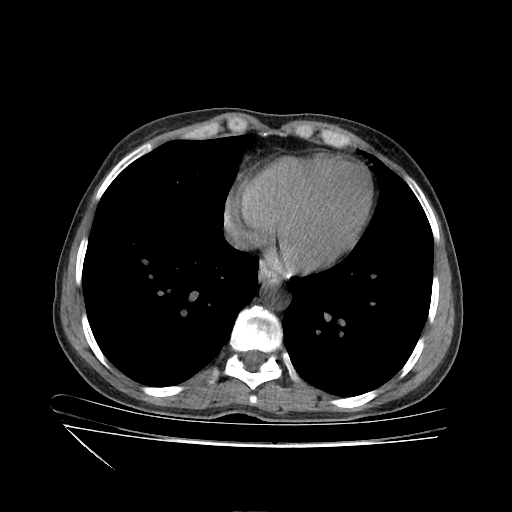

Reconstructed NATIVE CT scan (cycle consistency)

Full window (WL 1023.5, WW 4095 β†’ Low βˆ’1024, High +3071)

Actual HU range: [-1024.0, 702.5]